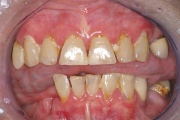

Sjögreni sündroomi võimalusele mõeldakse silmade ja suu kuivuse all kannatavatel patsientidel. Süsteemne haigus, mida iseloomustab kõigi eksokriinsete näärmete talitluse puudulikkus kroonilise põletikulise destruktsiooni tõttu.  Keratokonjunktiviit  Kserostoomia  Polüartriit Loe edasi »